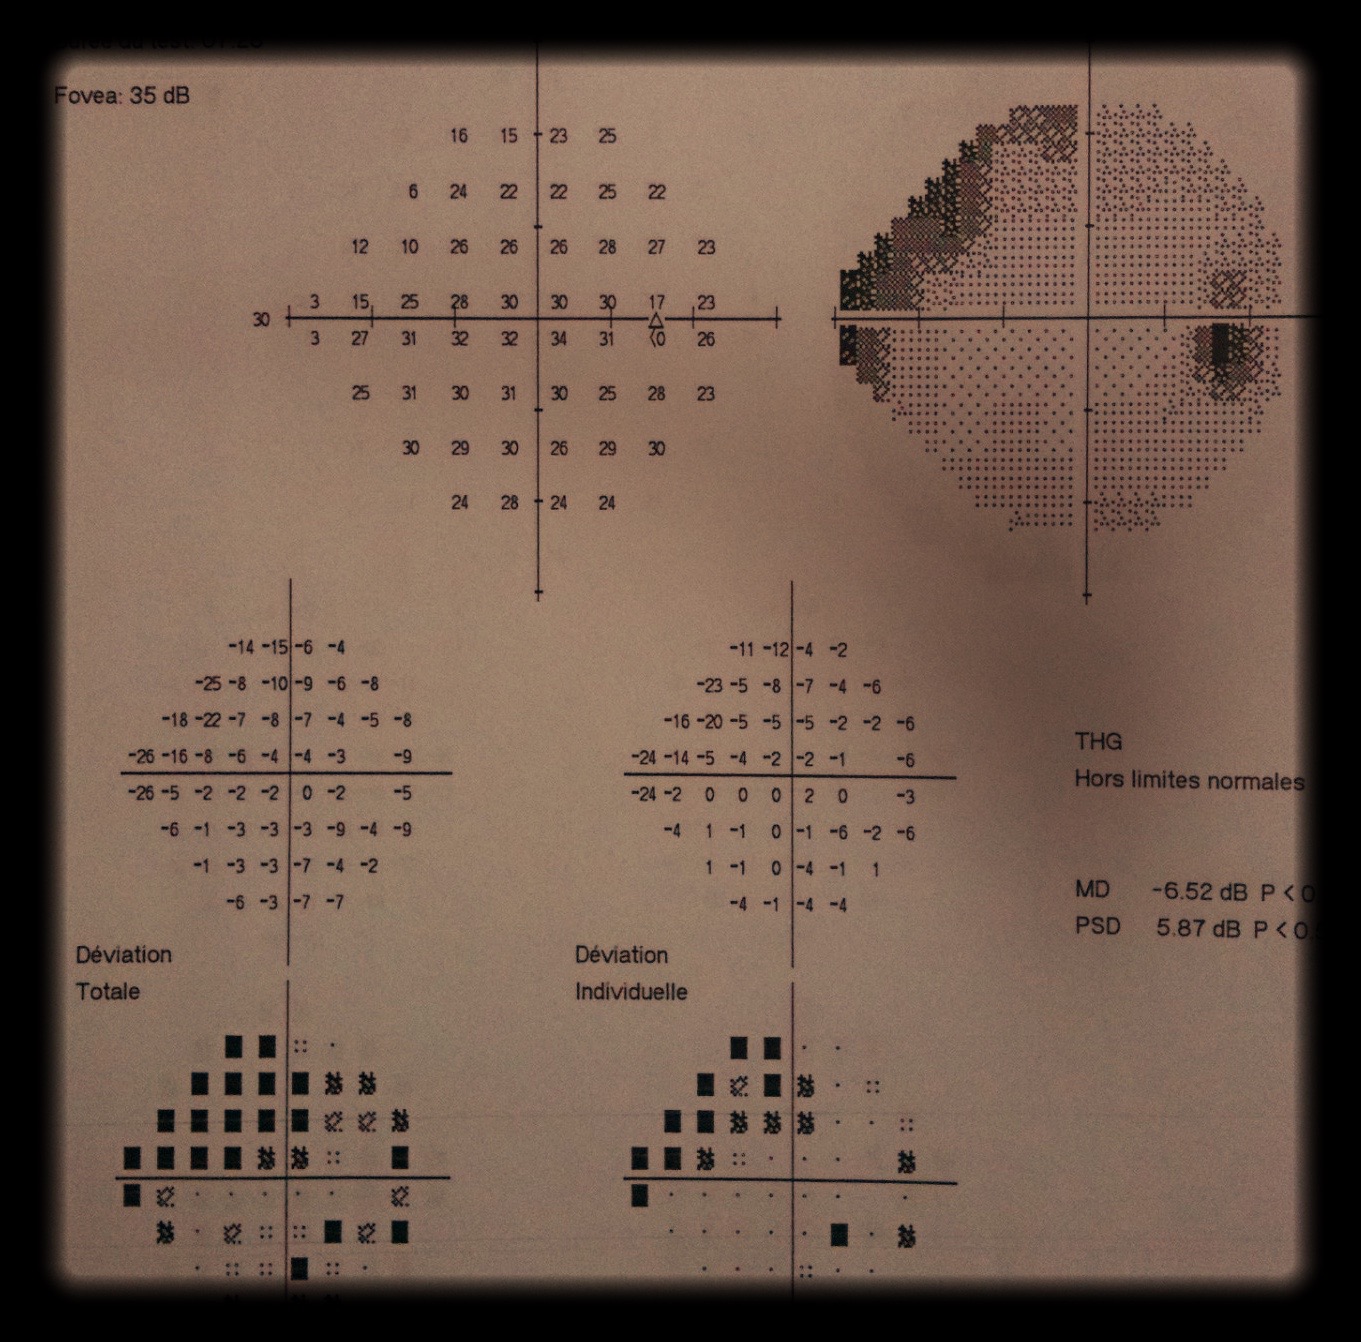

Glaucome :

bilan, suivi, contrôle de tension oculaire

- suivis de pathologies chroniques (glaucome,...),